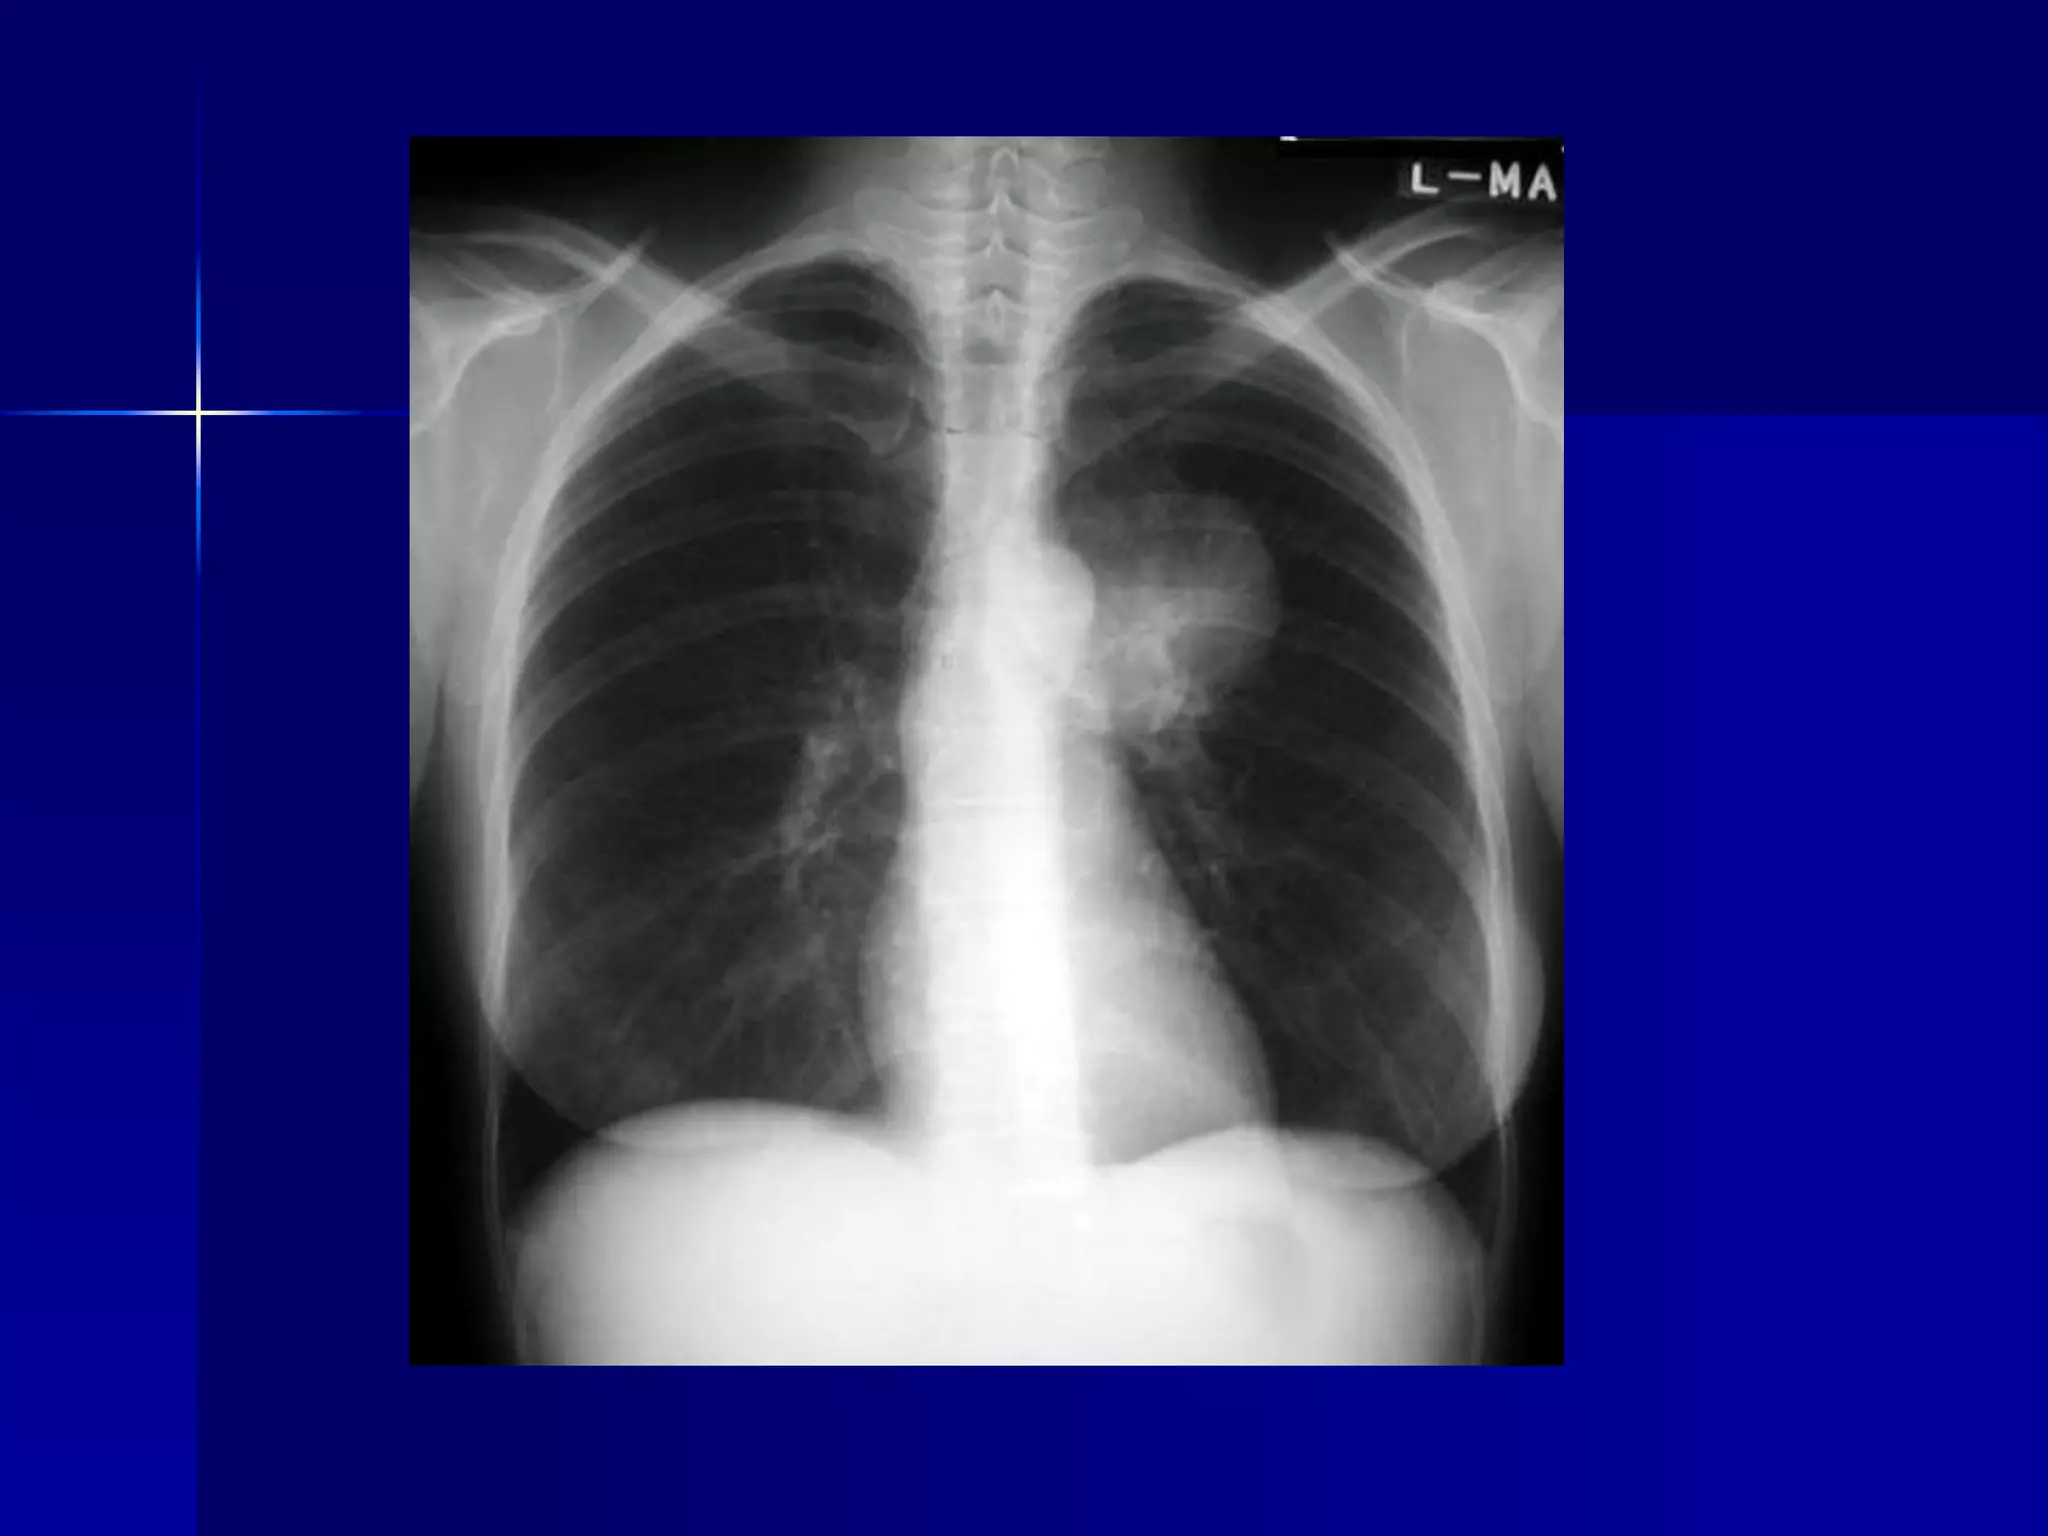

Sarcoidosis

 Alveolar Form

 Symmetrical hilar nodes

 Mediastinal nodes

 Multiple bilateral mass densities with

alveolar features

 Soft coalescing